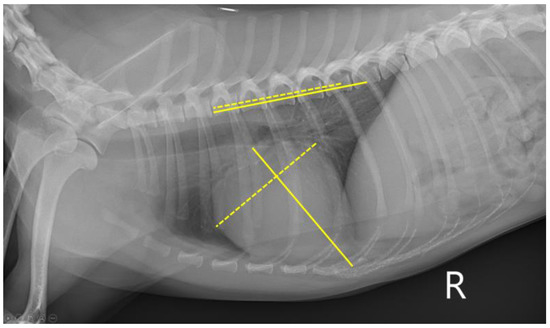

2.2. Thoracic Radiography

| VLAS | 1.40 (1.20–1.50) | 1.50 (1.40–1.60) | 1.90 (1.80–2.30) | <0.001 | a,b < c α,γ,ε |